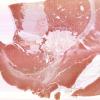

31C7 Cavernoma (Case 31) H&E 20X